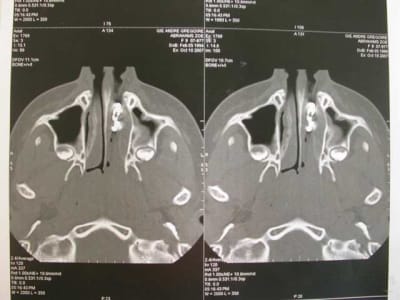

l'objet: une petite chainette boule métallique (celles qui sont accrochées à certains vetements et qu'on retrouve sur les bouchons de baignoire) complétement oxydée (noir de chez noir, avec diminution du diametre de certaines boules) .

temps de séjour estimé dans les fn: 4-5 ans

La maman de zoe vient en consultation, pour un contrôle semestrielle. Elle est enceinte de 8 mois, se porte bien , et rien de particulier ne doit être entrepris avant la fin de la grossesse. En fin de rendez-vous, elle me demande de jeter un œil sur Zoe. La petite agée de 9ans et demi présente une jolie classe III osseuse. J’en profite pour lui faire une panoramique. Là, à ce stade, vous avez tous vu le résultat. Je vérifie qu’il ne reste pas une barrette oubliée ou autre (nada), et préfère effectuer une nouvelle pano. Même résultat.

Je décide donc de faire réaliser un scanner et là c’est nouveau pour vous.

Une fois le scanner réalisé, je vois bien qu’il s’agit d’un objet composé de boules et l’adresse illico à son orl. Il la reçoit dans la foulée, et au vu du scanner, se refuse d’intervenir de peur de renvoyer plus loin l’objet. A son tour, il l’adresse à un hopital spécialisé enfants (Robert Debré). Au service ORL, ils tentent de retirer l’objet avec une pince (comme Dr House le faisait dans un épisode) et rien de neuf, aucune progression.